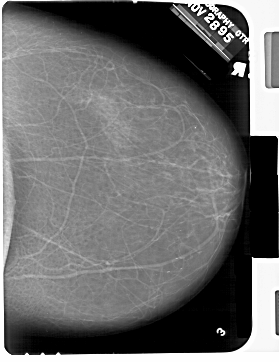

A_1332_1.LEFT_CC

LEFT_CC LINES 6871 PIXELS_PER_LINE 4951 BITS_PER_PIXEL 12 RESOLUTION 43.5 OVERLAY